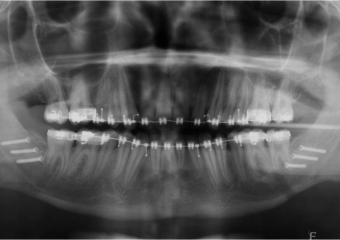

Raio x após cirurgia